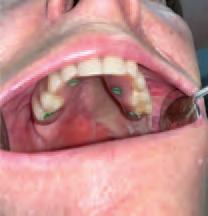

The zygomatic implant perforated (ZIP) flap for rehabilitation of patients with midfacial oncology defects: a report of three cases B. Martin, E. Cotter, C. Bowe, J.E. O’Connell

145 CLINICAL FEATURE